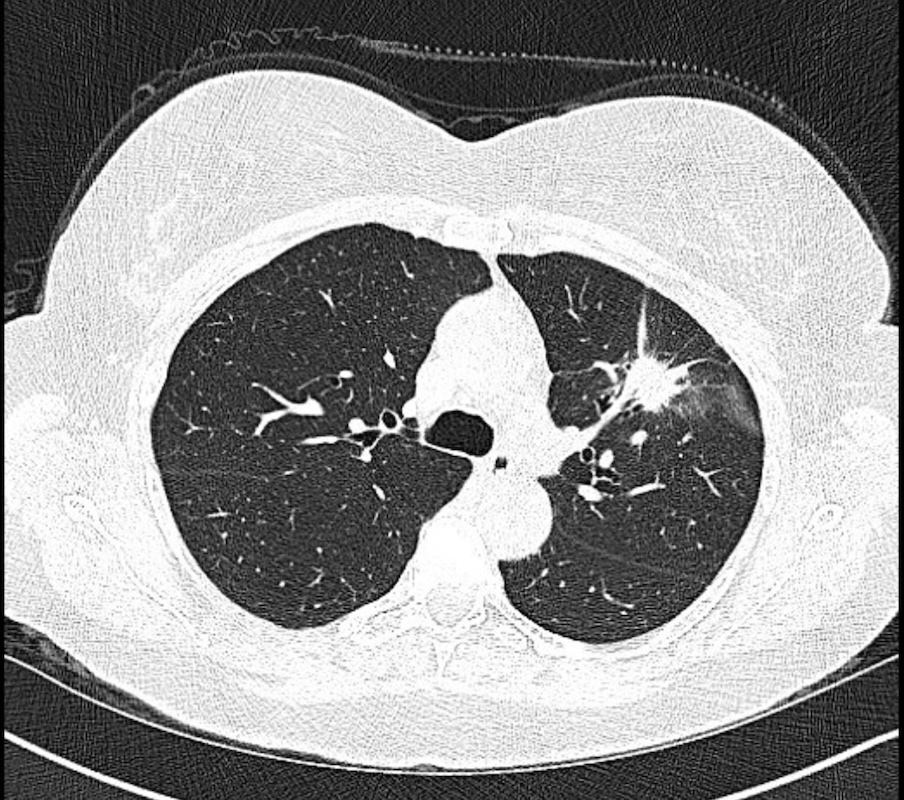

A multicenter prospective study of robotic-assisted bronchoscopy shows that RAB-guided sampling of peripheral pulmonary lesions compares favorably with results from sizable nonrobotic #bronchoscopy studies.

Read more in the August #JournalCHEST issue: hubs.la/Q03Cql920